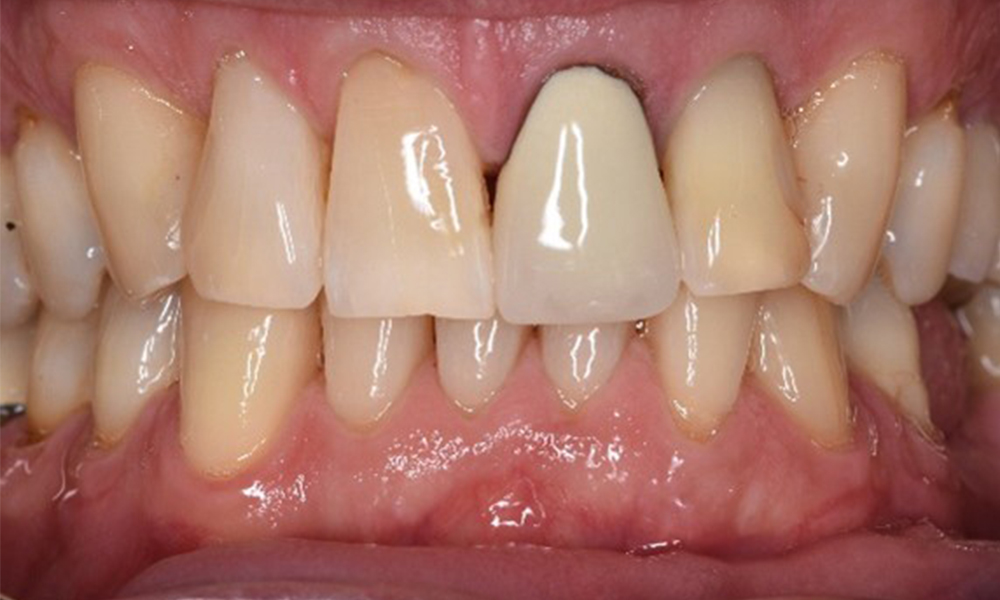

Patientenfälle nach IPCUm das Zusammenspiel der für den IPC definierten Bedarfs- und Risikofaktoren sowie die Auswirkungen einzelner Faktoren zu illustrieren, dienen nachstehende Fallbeispiele*. Die mundgesunde DiabetikerinEine 51-jährige mundgesunde Diabetikerin stellt sich zur Präventionssitzung vor. Die Blutzuckerwerte sind stabil bei einem HbA1c = 6,2%, folglich gilt sie mit dem entsprechenden Medikament Metformin (Antidiabetikum) als suffizient eingestellt. Die Patientin hat keine bestehenden Versorgungen oder orale Vorerkrankungen. Anhand der aktuellen Befunde lässt sich eine Gingivitis bei sonst stabilem parodontalem Zustand (Stage II, Grad B) feststellen. mehr Infos Fallpräsentation: Management komplexer ZahnprothetikEs ist längst bekannt, dass Mundgesundheit und Allgemeingesundheit in direktem Zusammenhang stehen und einen zum Teil bidirektionalen Einfluss aufeinander haben. Die Berücksichtigung beider Faktoren sind bei der Planung der oralen Prävention und Therapie der Patienten in der Zahnarztpraxis unabdingbar. Dabei ist oberstes Ziel, die Gesundheit und die Lebensqualität der Patienten sowohl aus zahnmedizinischer -und medizinischer Sicht zu erhalten. mehr Infos Der (mund)-gesunde Patient mit ImplantatenDer 55-jährige Patient gibt in der Anamnese an, keine Allgemeinerkrankungen zu haben und keine Medikamente einzunehmen. Die Lebensgewohnheiten des Patienten sind ebenfalls unauffällig. Der Patient hat einige zahnärztliche Restaurationen und zwei Implantate (2. und 4. Quadrant). Anhand der aktuellen Befunde lässt sich eine Gingivitis bei stabilem parodontalen Zustand am reduzierten Parodont (Stadium III, Grad A) feststellen. mehr Infos Der gesunde Patient mit parodontaler Vorerkrankung & PeriimplantitisEin 52-jähriger Patient stellt sich zur Präventionssitzung vor. Der Patient hat keine Allgemeinerkrankungen und nimmt keine Medikamente ein. Er hat verschiedene zahnärztliche Versorgungen und zudem zwei aktive kariöse Läsionen. Außerdem verfügt der Patient über vier Implantate (2., 3. und 4. Quadrant). Es zeigt sich eine parodontale Vorerkrankung (Stadium IV, Grad B). Derzeit herrschen stabile parodontale Verhältnisse, lediglich am Implantat regio 36 zeigen sich Sondierungstiefen (ST) von 5 mm. Zudem lässt sich eine Gingivitis feststellen. mehr Infos Der Diabetiker mit ParodontitisDieser Fallbericht eines 52-jährigen Mannes mit Typ-2-Diabetes und Parodontitis hebt hervor, wie durch individuelle Vorsorgemaßnahmen, die Gesundheit des Zahnhalteapparates erhalten bzw. das Fortschreiten der Erkrankung kontrolliert werden kann. mehr Infos Der 28-jährige Raucher mit ZahnerosionenDieser Fallbericht eines 28-jährigen Rauchers mit Zahnerosionen zeigt die Bedeutung personalisierter Patientenprofile. Er unterstreicht die Notwendigkeit, sowohl die Mundgesundheit als auch die allgemeine Gesundheit zu berücksichtigen, um Erkrankungen der Zähne bzw. des Zahnhalteapparates effektiv zu verhindern. mehr Infos Der Endokarditis-Patient mit aktiven KariesläsionenDer Patient ist 39 Jahre mit Z.n. Herzklappenersatz wegen Klappenfehlers und Endokarditis. Als Antikoagulans (Gerinnungshemmer) wird regelmäßig ASS 100 eingenommen. Aus dem Bereich Lebensstil ist die Ernährungsweise als kariesfördernd einzustufen, da mit hoher Regelmäßigkeit zuckerhaltige Lebensmittel sowie sechs bis sieben Mahlzeiten täglich verzehrt werden. Die Mundgesundheit des Patienten zeigt ein mittleres Kariesrisiko mit aktiven Läsionen. Das Parodontitisrisiko ist niedrig, es besteht eine Gingivitis. Es ergeben sich folgende Empfehlungen für die Prophylaxebehandlung. mehr Infos Die gesunde Patientin mit parodontaler VorerkrankungDie 68-jährige Patientin hat keine zahnmedizinisch relevanten allgemeingesundheitlichen Vorerkrankungen oder Medikation, auch aus dem Lebensstil ergibt sich kein besonderes Risiko. Die Patientin hat zwei Implantate (3. Quadrant, seit fünf Jahren) sowie eine parodontale Vorerkrankung (Parodontitis Stadium IV, Grad B) mit Zahnverlust. Derzeit zeigen sich stabile parodontale Verhältnisse. Für die Prophylaxesitzung ergeben sich vier Empfehlungen in den Bereichen Anamnese/Befund, Motivation/Instruktion, der Wahl der geeigneten Instrumente und für Resümee/Folgetermin. mehr Infos